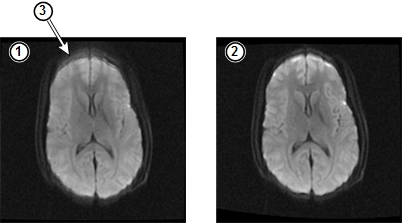

The following illustration shows the effects of these high order eddy currents and the results of HOEC correction. (The images have been adjusted to make the defect more apparent.)

Figure 1. Example HOEC Uncorrected and Corrected Single-Spin Echo Images

| 1 | Uncorrected SSE image | 2 | HOEC corrected SSE image |

| 3 | Blurring related to mis-registration due to high order eddy currents |